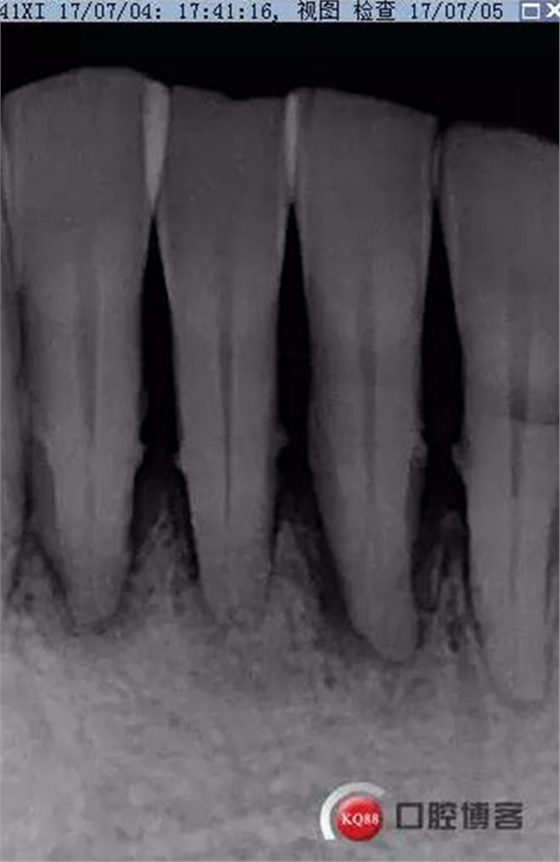

X線示牙槽骨吸收,下頜前牙區(qū)可見齦下牙石影像,牙槽骨吸收至根尖1/3,根周透射影像。

檢查:下頜前牙區(qū)PD1-3mm,牙齦色澤尚可,舌側(cè)齦緣可見少量軟垢附著。31松II°,32、41、42松I°+。

X線示根周透射影骨密度增高。